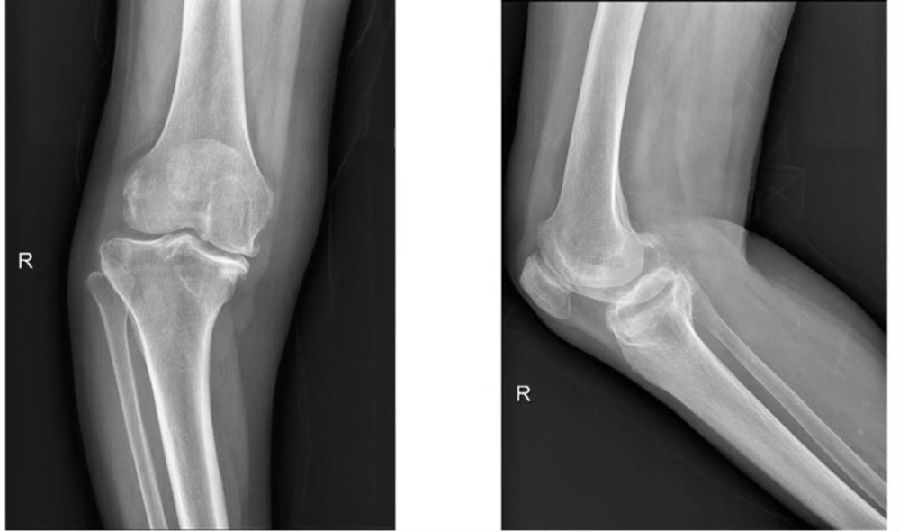

一期双侧内翻膝aMA+arKA典型病例一例。王x,女性,80岁,因“双膝疼痛10余年,加重3月”入院。

PE:双膝内翻畸形,左膝稍肿胀,左膝活动度屈曲100°,伸直0°,内侧关节间隙压痛(+),浮髌试验(-),右膝稍肿胀,活动度屈曲100°,伸直0°,内侧关节间隙压痛(+),浮髌试验(-),双下肢皮肤感觉及末梢血运正常。

手术方案:左侧aMA,右侧arKA

图6图7 术前

图8 术前影像(R)